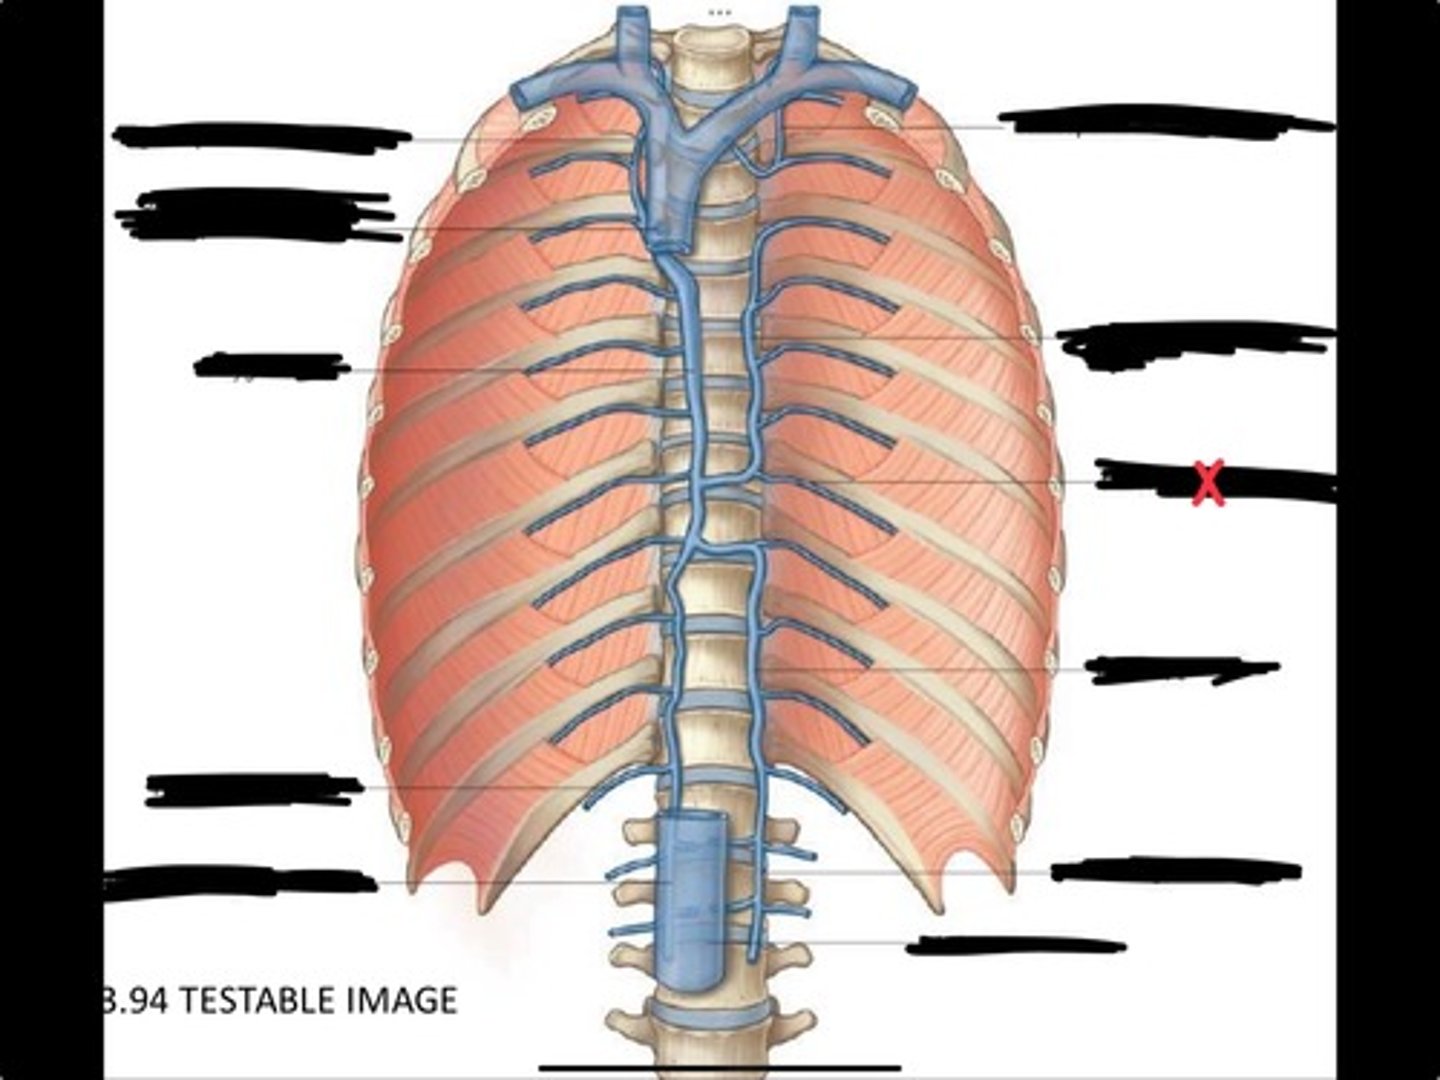

Right ascending lumbar vein

Right subcostal vein

Azygos vein

Opening of the azygos vein into superior vena cava

Right superior intercostal vein

Left superior intercostal vein

Accessory hemiazygos vein

Posterior intercostal vein

Hemiazygous vein

Ascending lumbar vein